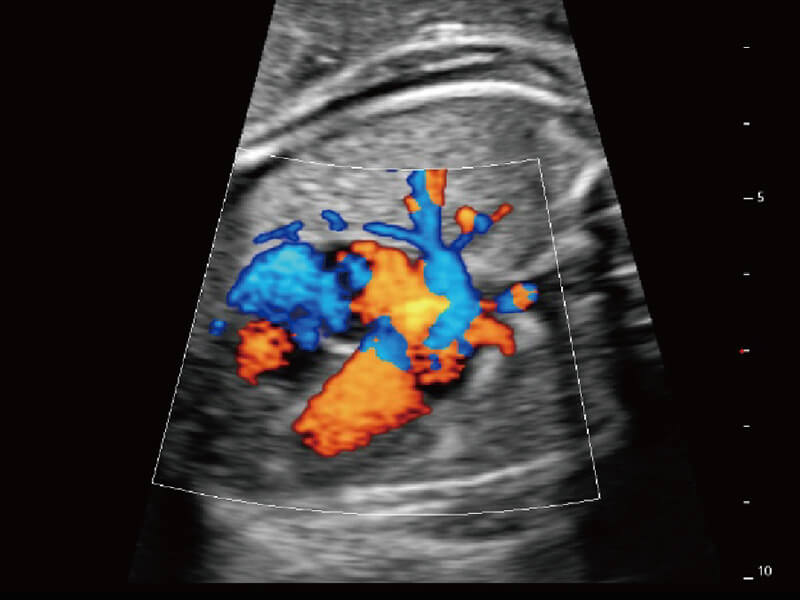

Micro F 显微血流成像 明察秋毫